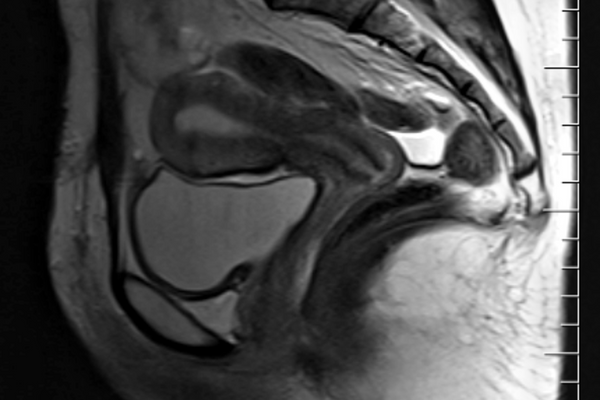

Why Does Endometriosis Cause Painful Sex?

About 50% of people with endometriosis experience pain with penetrative sex o...